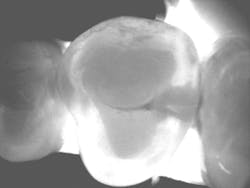

Before I began prepping for the crown, I used CariVu. On the images, I saw not only a crack on the tooth that was to be crowned, but also clear caries on the adjacent tooth (figure 6). During treatment, I snapped a picture of the preparation on tooth No. 2 with an SLR extraoral camera (figure 7). I took an additional photo midtreatment to show how far the cavity had progressed into the dentin. The bitewing didn't show any of this decay. This caries detection technology gives me a great opportunity to tell patients that I found a cavity that we would not have known about until it caused trouble. There is no surprise later and no apologies for missing an early lesion.

Figure 6: CariVu image clearly shows mesial decay on tooth No. 2.